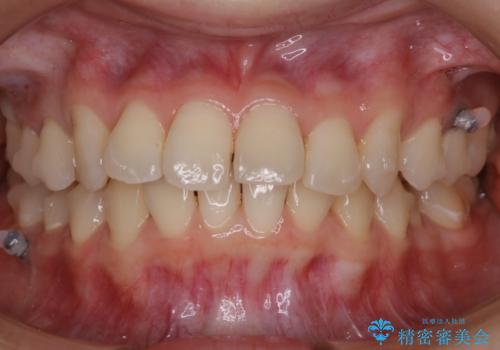

- 矯正装置

- マウスピース(インビザライン)

- 治療期間

- 1年10ヶ月

抜歯は全く必要のないレベルのガタつきだったため、マイクロインプラントを用いて歯全体を後方に移動させていくことできれいな歯並びを獲得することができました。

マウスピースとマイクロインプラントを組み合わせることで、抜歯をしなくても歯並びを治すためのスペースを作ることができます。奥歯から順に移動させていくので前歯に変化が出るまでには時間がかかりますが、どの分健康な歯を抜歯することなく理想的な歯並びを手に入れることができます。